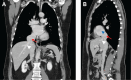

Incidental Aneurysm of the Suprahepatic IVC